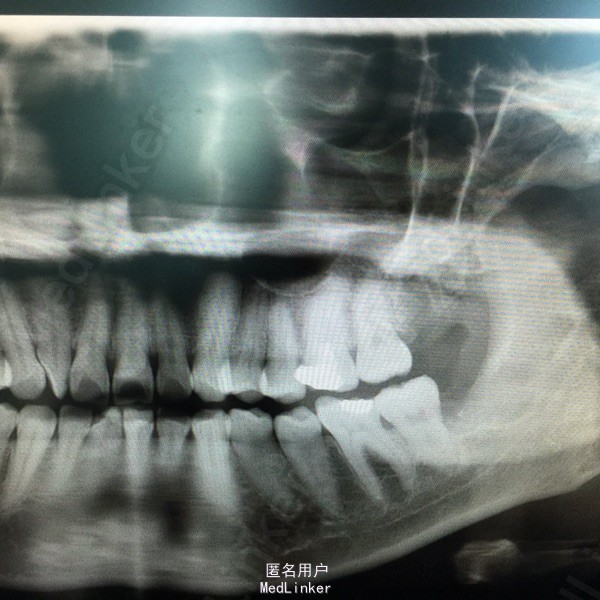

患者左下第三磨牙区反复肿胀疼痛史,口服抗生素三天,无肿胀、疼痛。

查:38近中倾斜,牙龈无红肿、压痛,开口度良好,全景牙片示:38近中水平阻生,根尖无明显炎症,近中根尖紧邻下牙槽神经管。

诊断:38近中水平阻生。 处理:1.局麻下拔除。 2.抗炎对症治疗。 3.保持口腔卫生,一周后拆线、复查。